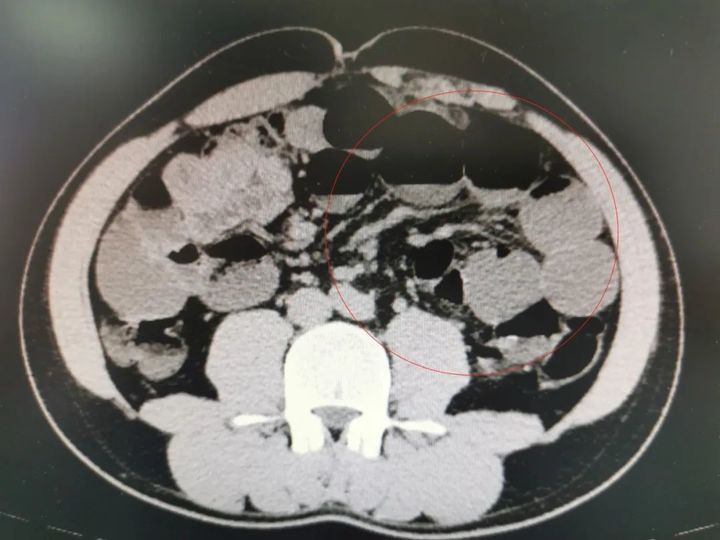

小汪小肠梗阻影像图